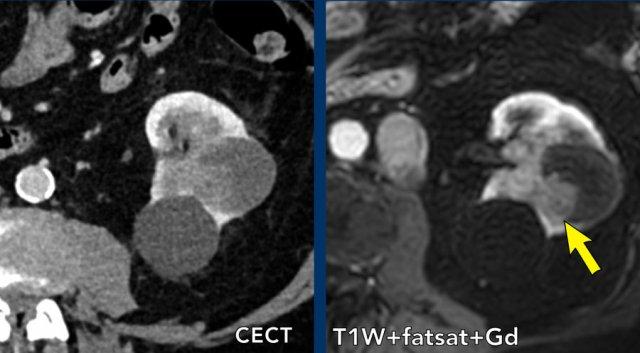

Ca lâm sàng 4

Hình chụp CT thì tĩnh mạch cửa cho thấy một tổn thương dạng nang không đồng nhất ở thận trái.

Vùng tăng tỷ trọng có ngấm thuốc trên ảnh chuỗi xung T1W có ức chế mỡ, phù hợp với một nốt đặc trong nang Bosniak 4.